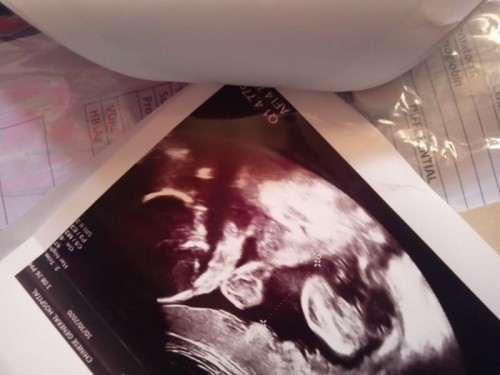

mismong si baby na po yan diba? Ulo, kamay at paa pero bat po parang ang payat po ng katawan?Thanks

basahin mo ung growth tracker nitong app mommy. asa over 30 weeks bago pa lang magdevelop ng fats si baby. other than that, usually ineenterpret yan ng nagsono or ng OB mo mismo. or you can directly ask them din.

Hinde ba ini-explain sayo ng sono kung ano yan habang ini-ultrasound ka?